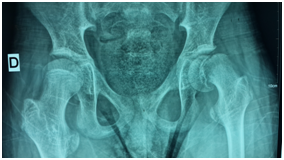

The admission examination finds a hemodynamically and respiratory-conscious conscious child, apyretic, weight at 40kg with extreme spasticity of the four limbs flexing. Both hips were adducted flexed at 80°C with pain in the mobilization of the left hip. The radiograph of the pelvis of the face showed a shift of the superior femoral epiphysis with respect to the metaphysis at the level of the left hip (Figure 1). The child was operated on day 2 of admission with a screw in situ (Figure 2). Operative follow-up was simple with radiological control, and the child was summoned for a month to check.

Figure 2 Radiograph of the pelvis in profile (frog incidence) showing the postoperative aspect after fixation in situ.